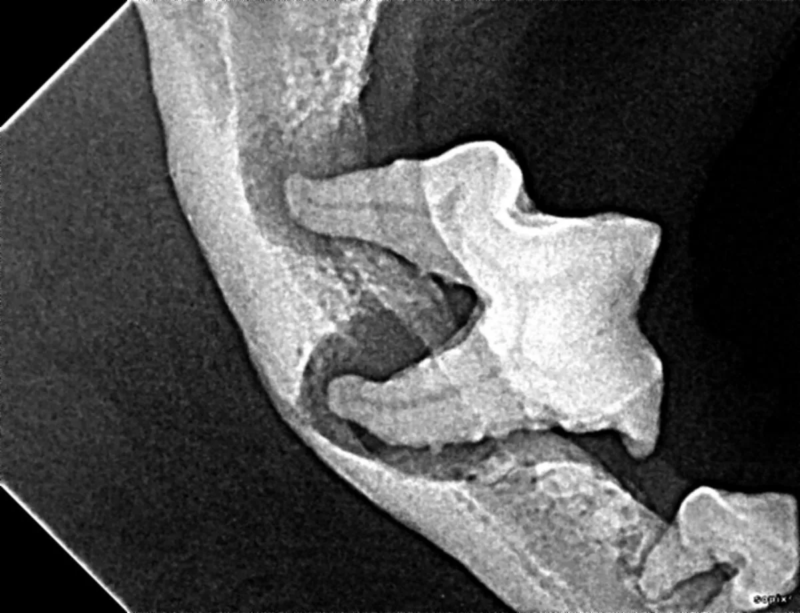

Cone Beam Computed Tomography

The Center now provides advanced imaging via cone beam CT. Cone beam CT is excellent for visualization of bony structures of the skull, nasal cavity, teeth, and ears. Cone beam CT is especially helpful for diagnosing dental disease and evaluation of jaw fractures. It can also be useful for evaluating the sinuses and tympanic bulla. Cone beam CT can be used in conjunction with nasal biopsy and culture to evaluate nasal discharge whether chronic or acute.